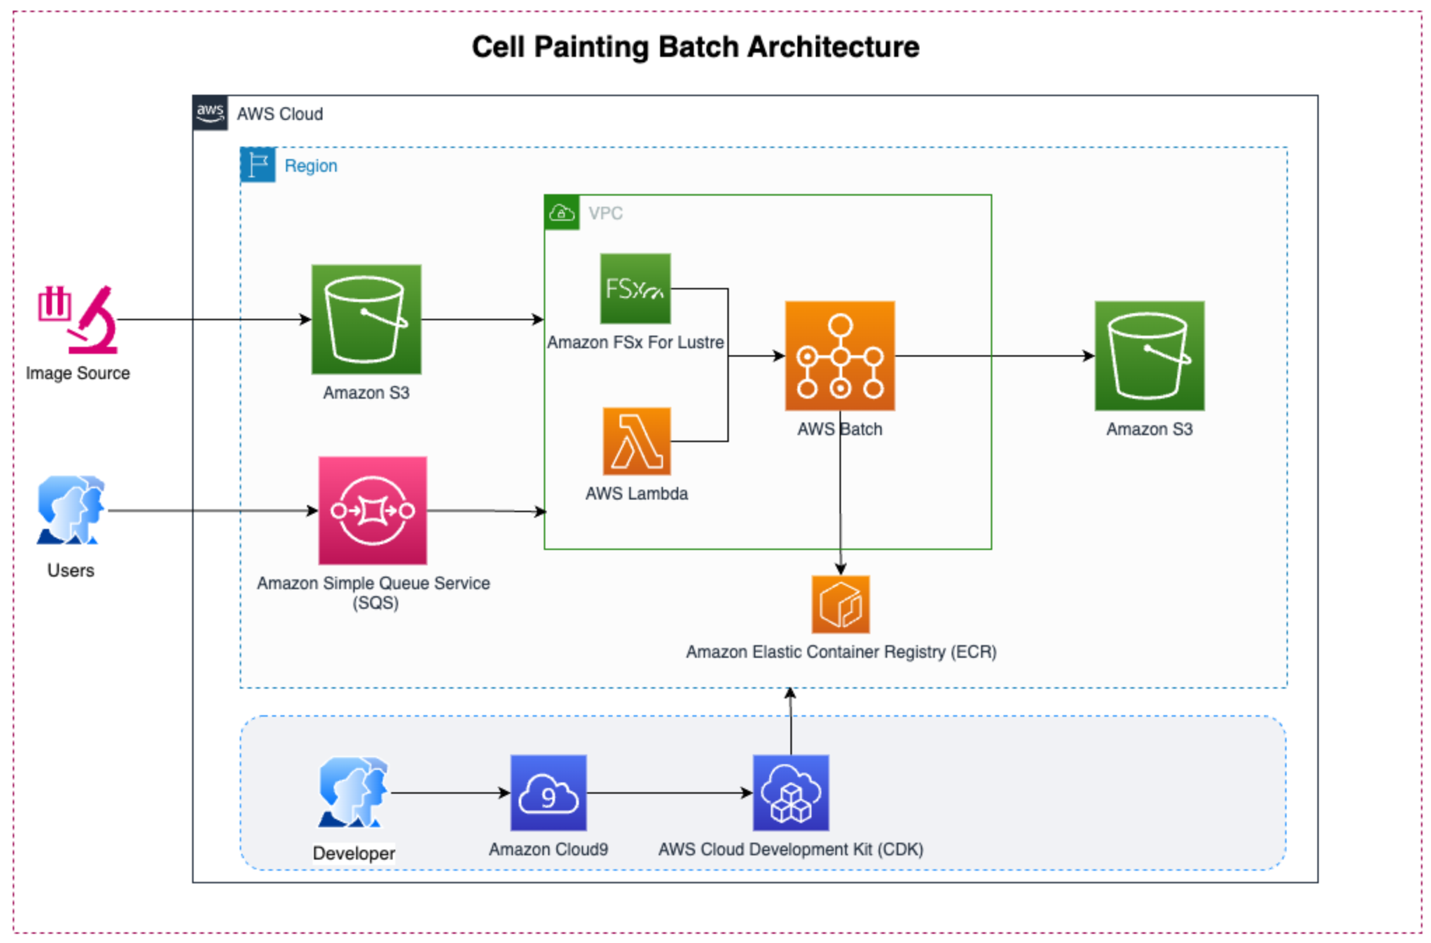

Figure 1 – This diagram shows an Amazon S3 bucket to drop images from microscopes. When a user submits an SQS message, it triggers AWS Lambda. The Lambda function submits an AWS Batch job based on a container image pulled from the Amazon Elastic Container Registry (ECR). AWS Batch processes the images and publishes the results to an Amazon S3 bucket for further analysis.

To address these challenges, AWS solution architects worked with life sciences customers to develop a new solution called Cell Painting Batch (CPB). CPB uses CellProfiler image from Broad Institute to run CellProfiler Pipelines on AWS in a scalable and distributed architecture. CPB enables researchers to run large scale image processing tasks without worrying about complexity involved in infrastructure management. Additionally, CPB solution is built using AWS Cloud Development Kit (CDK) which makes it easy to deploy and manage infrastructure.

The entire workflow is automated, once images are uploaded, an Amazon Simple Queue Service (SQS) message is sent which triggers the entire process, from image processing to result storage. This provides researchers with an efficient, automated, and scalable solution for their large-scale image processing needs.

- On the receipt of an SQS message, an AWS Lambda function is automatically triggered. This function’s primary role is to initiate the AWS Batch job for the particular image processing request.

- AWS Batch evaluates the job requirements. Depending on the task, AWS Batch dynamically provisions the necessary Amazon Elastic Compute Cloud (EC2) instances.

- The specified container image, stored in Amazon Elastic Container Registry (ECR) is fetched. Within AWS Batch, this container executes, running the defined CellProfiler pipeline. Amazon FSx for Lustre integrated with the S3 bucket ensures data is promptly available to containers.